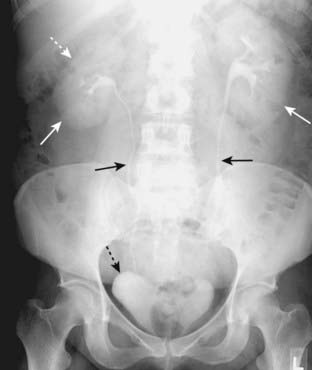

Figure 13-2 Normal prone abdomen.

In the prone position, the ascending and descending colon and the rectosigmoid—all posterior structures—are the highest parts of the large bowel and thus most likely to fill with air. There is air seen in the S-shaped rectosigmoid (solid black arrow) and throughout the remainder of the colon (solid white arrows).

Figure 13-7 Location of large bowel.

The large bowel usually occupies the periphery of the abdomen. The small bowel is located more centrally. Here, the large bowel (solid black arrows) contains a normal amount of air. The liver occupies the right upper quadrant and normally displaces all bowel from this area.